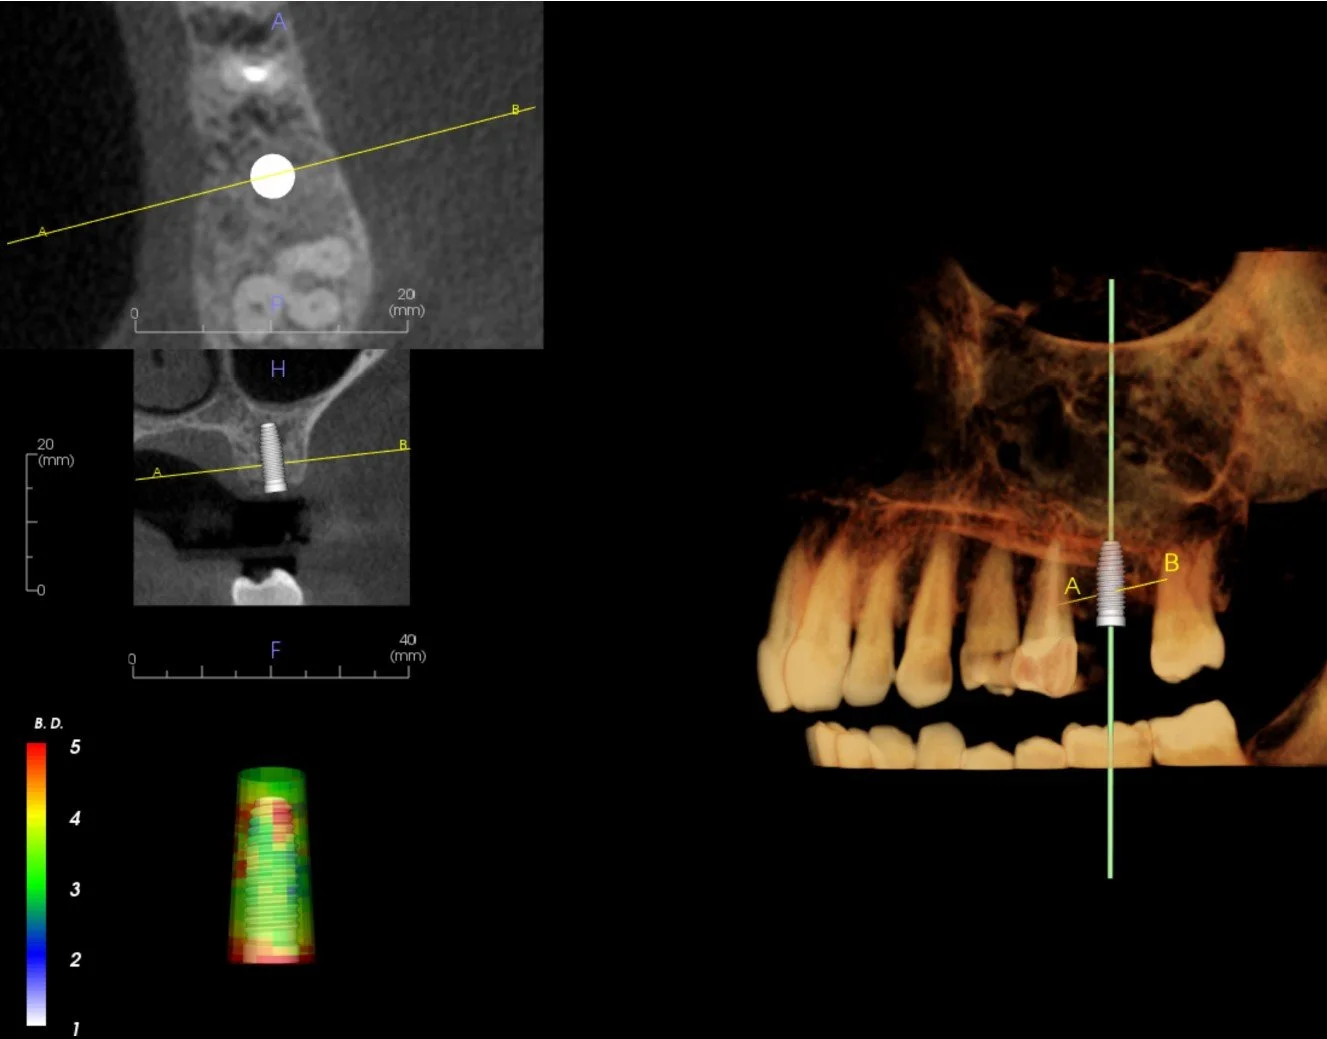

Visualization of virtual dental Implant Placement  in  Cone Beam CT image

• Orbit's Implant Plans are created in 3 Shape Implant Studio planning environment. by an experienced dental professional in collaboration with the implant dentist or specialist. The plans are prosthetically driven and include an interactive planning session with the referring clinician. The resulting plan can be used to create a surgical guide by Orbit or or by a preferred dental laboratory.